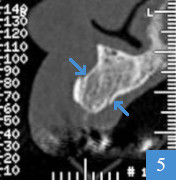

Le sinus lift en image

coupe panoramique de dentascanner, dent 26 absentecoupe coronale de dentascanner, hauteur osseuse de 3 mm seulement

Dentascanner initial

1a : 1ère molaire supérieure gauche (dent 26) absente et os résiduel du maxillaire fin

1b : os sous le sinus mesuré à 3 mm de hauteur ; pose d'un implant impossible en l'état